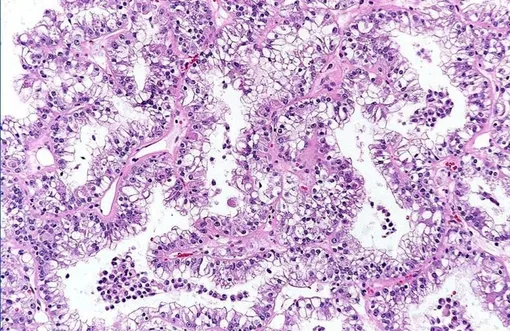

Транслокационная карцинома почки (tRCC) — редкое и агрессивное заболевание, поражающее детей и молодых взрослых. При делении клетки (митозе) хромосомы могут ошибочно обменяться своими фрагментами. В этом случае ген TFE3 может сливаться с другими генами. В результате образуются активный ген, который кодирует химерные белки-онкофузии. Эти белки постоянно активируют гены роста и провоцируют развитие опухоли. Это было известно, но ученые не понимали механизм, с помощью которого химерные белки запускают бесконтрольный рост опухоли.

Теперь ученые обнаружили, что химерные белки привлекают молекулы РНК для создания каркаса особых структур — конденсатов. Эти капли собирают важные молекулы в плотные карманы, которые становятся центрами активации генов роста опухоли. «РНК — не просто пассивный посредник, а активный участник строительства этих конденсатов», — отметил профессор Юн Хуан, старший автор работы. Ученые также выявили и другой важный белок — PSPC1, укрепляющий эти капли и усиливающий их роль в развитии опухоли. Работа опубликована в Nature Communications.